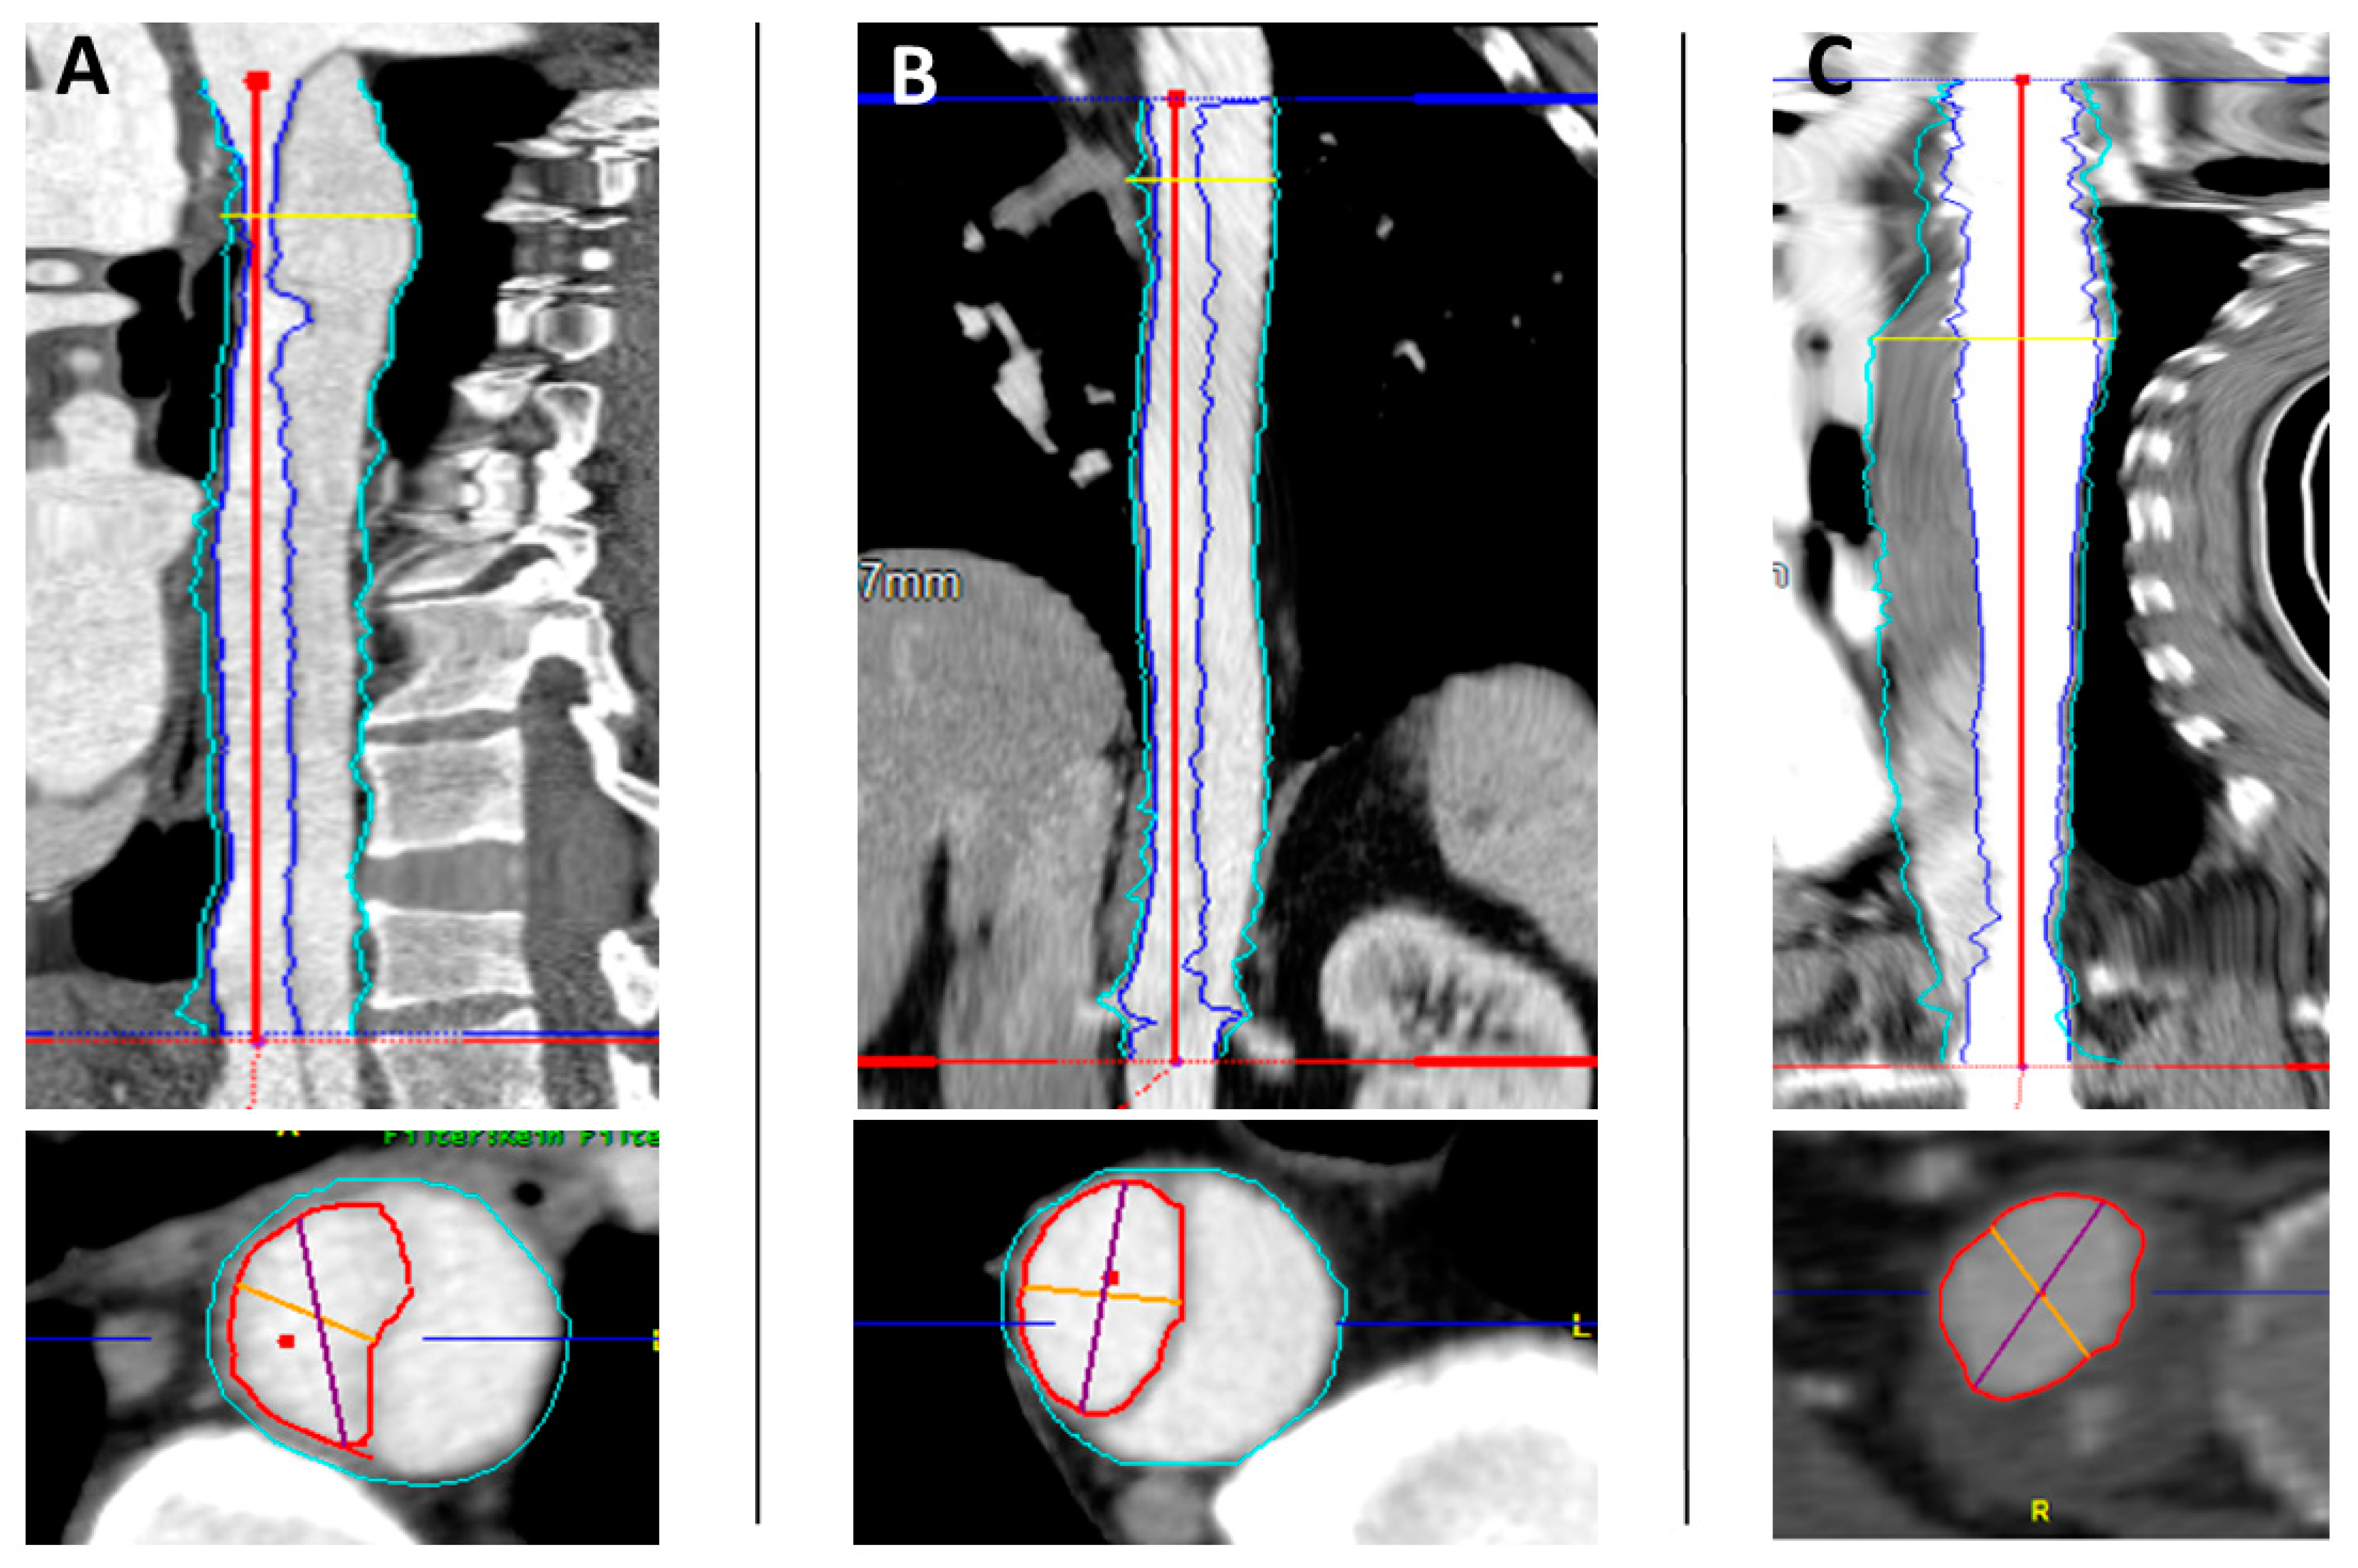

2.2. Volume Measurement